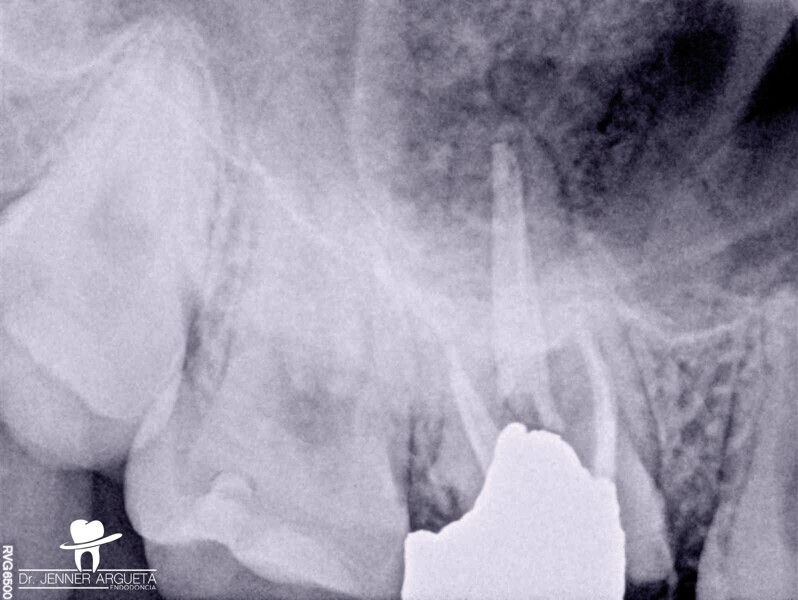

La patiente s’est présentée au cabinet huit mois plus tard avec des signes et des symptômes de nécrose pulpaire et d’abcès périapical aigu mis en évidence par une radioclarté. La zone rétromolaire était bien cicatrisée (Fig. 6). Dans des cas comme celui-ci, où la structure coronaire est encore intacte, il est conseillé de recourir aux nouvelles techniques endodontiques et d’adopter une approche conservatrice du traitement endocanalaire afin d’obtenir de meilleurs résultats. Le puits d’accès endodontique a été créé au moyen de fraises à haute vitesse et d’inserts ultrasoniques. Le protocole de nettoyage et de mise en forme a été réalisé à l’aide de canules et de limes flexibles en alliage à mémoire de forme contrôlée (Aurum Blue, Meta Biomed), dont les propriétés sont particulièrement importantes lors de la pénétration dans les canaux radiculaires par l’accès conservateur (Figs. 7a et b).

Les limes endodontiques dont l’alliage est stabilisé en phase martensitique (mémoire de forme contrôlée) sont en effet dotées d’une meilleure résistance à la fatigue cyclique.11, 13, 14 Les canaux radiculaires ont été obturés au moyen d’un ciment de scellement endodontique à base de silicate de calcium activé par ultrasons (CeraSeal et EQ-S, Meta Biomed) et de gutta-percha (Figs. 8a–c). Cette étape du traitement peut s’avérer délicate en présence d’un accès endodontique de très petite taille.